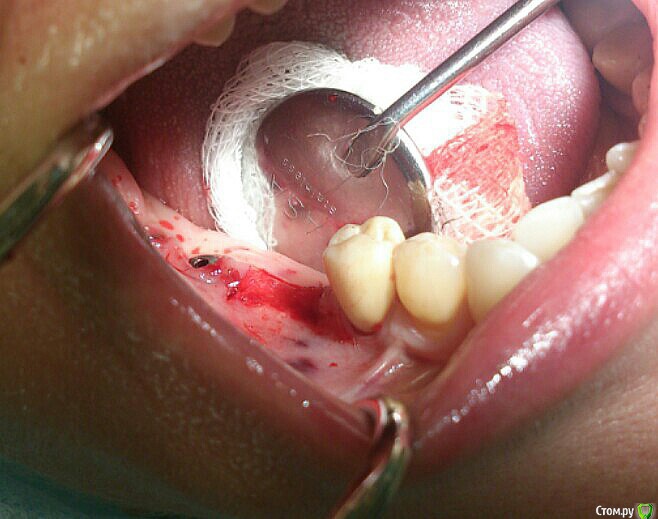

andrey_1965 Опубликовано 21 декабря, 2015 Поделиться Опубликовано 21 декабря, 2015 Ну как результат ?1.-диэпителизация подворот лоскута очень удобно,но опасно для резбы через неделю.язычно-механическая травма через 10 дней через 3недели. На временных доформирую рельеф.2. вроде ничего нештатного через 2недели A-PRF через 5недель убрал все,закрыл мембраной A-PRF две поперек,одна в доль через неделю через 13дней через 21день. Следующий осмотр будет на сроке 5 недель(думаю все сравняется) 3. через неделю 2недели 3недели,на дистальных отмываю помойку4 недели Ссылка на комментарий